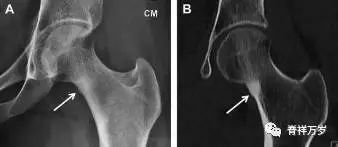

股骨颈应力性骨折在参加耐力运动的运动员中常见,且常发生在股骨颈压力侧。股骨颈基底部发现一垂直于骨皮质的线性硬化带可诊断这种类型的疲劳性骨折(图 7)。

图 7 长跑运动员股骨颈应力性骨折。X 片(A)和冠状位 CT 多维重建(B)图像示穿过股骨颈内侧皮质中的透亮区(箭头),周围硬化。骨折垂直于皮质

股骨颈张力侧的应力性骨折有可能发展为完全骨折(图 8)。

图 8 进食障碍患者股骨颈应力性骨折的张力侧。A 正位片示股骨颈完全骨折。B 2周前的 X 片示局部骨量减少,正是后来发生骨折的位置(箭头)